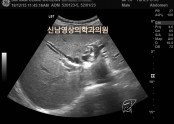

• 췌장에 혹, 간 낭종, 상복부 초음파

•  복부는 배를 말하는 의학용어입니다.의학용어는 쉬운 말도 어렵게 하지요?상복부라는 뜻은 바꿔 말하면 배의 윗부분을 말하는 것입니다.하복부는 배의 아랫부분이 되겠지요. 왜 복부를 상,하로 나눴을까요?상부에는 간, 쓸개, 췌장, 비장, 신장이라는 장기가 위치해…